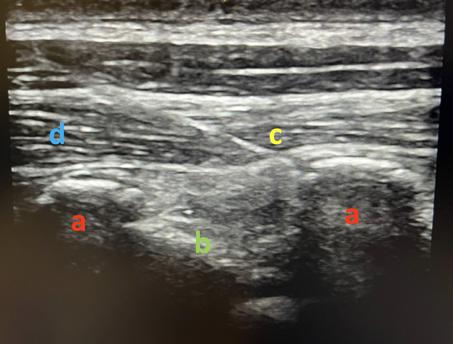

Table des illustrations

1. Korte, Wolfgang: Moderne Gerinnungsdiagnostik: wie hilft sie uns? http://www.anaesthesie-stgallen.ch/ Informationen_fuer_Fachpersonen/Fruehere_Veranstaltungen/IPS_Symposium_2008/05Korte.pdf

2. Görlinger K, Bergmann L & Dirkmann D. Coagulation management in patients undergoing mechanical circulatory support. Best Pract & Res Clin Anaesthesiol. 2012;26:179-198.

3. et 4. Gauger MS, Kaufmann P, Kamber F et al. Rotational Thromboelastometry Values After On-Pump Cardiac Surgery – A Retrospective Cohort Study. Semin Cardiothorac Vasc Anesth. 2022;26:209-220.

Laufbahnplanung auf

Die ideale Plattform für Berufs- und Bildungsprofile von Gesundheitsfachpersonen, weil

•alle Diplome und Zeugnisse an einem Ort zentral und elektronisch abgelegt sind

•ein stets aktueller Lebenslauf generiert werden kann